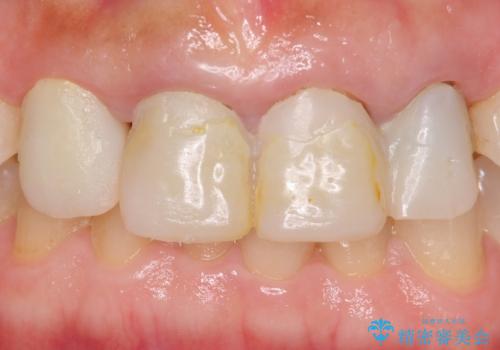

自然な前歯にしたい ジルコニアクラウンでの修復

- 前歯を綺麗にしたいとのことで来院されました。

色調・適合ともに改善するために一度被せ物を外し、歯の形を整えた後に新しい被せ物を装着していきます。

歯ぐきの炎症を抑えつつ、被せ物と歯との境目がわからなくなるよう被せ物を装着しました。

審美性が大変改善されたことで患者様にもご満足いただけました。